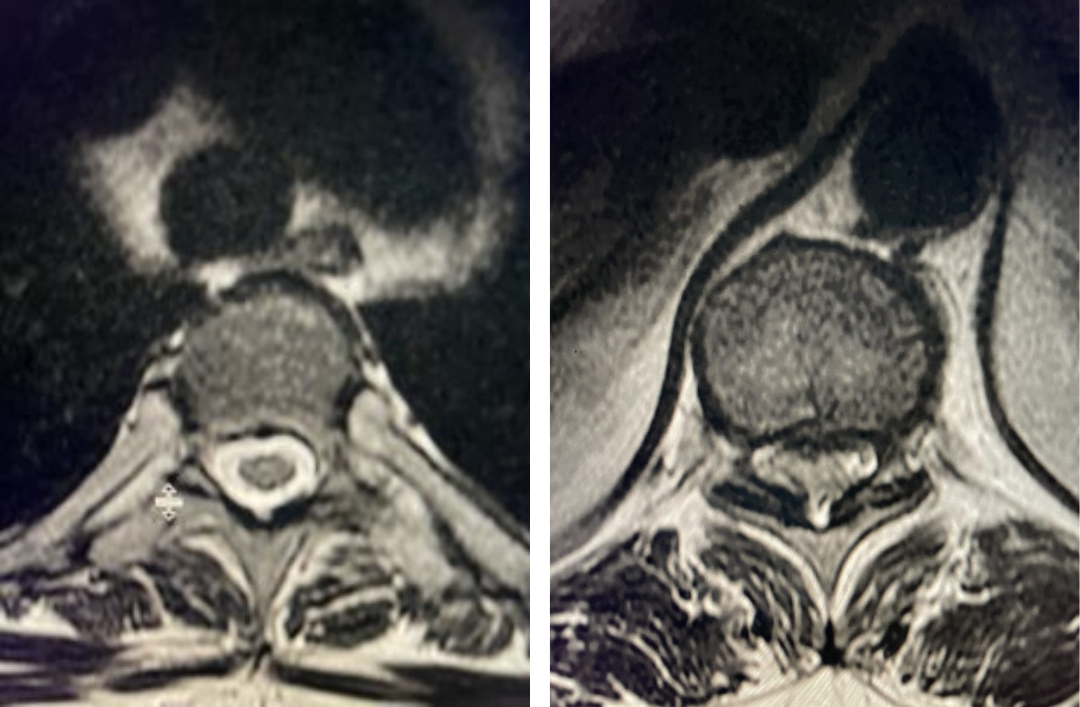

Fig 6: Axial T2-weighted lumbar MRI revealing a large extraforaminal disc herniation with severe compression of the left L3 nerve (red arrow).

Fig 7: Sagittal T2-weighted lumbar MRI with side by side comparison of the normal open right L3-4 foramen (red arrow) compared to the left L3-4 foramen filled with a large disc fragment (red arrow).

Here is a case of an extraforaminal disc fragment causing severe pain and weakness: This 60-year-old male presented with severe anterior thigh pain, numbness, and weakness for 3 weeks. He had failed epidural steroid injections. His left leg buckled when he walked. Imaging revealed a massive left L3-4 extraforaminal disc herniation, beyond the facet (Fig 6). This was severely compressing the left L3 nerve root in the L3-4 foramen (Fig 7). It was felt that the patient required surgery, as he would not be able to participate in physical therapy and had a neurological deficit. We performed an extraforaminal approach and removed a massive disc fragment that was revealed as the intertransverse membrane was reflected from the L4 transverse process-facet junction. We were able to visualize the L3 spinal root exiting above that had been compressed by the large fragment we removed (Fig 8). The patient post-op had a dramatic improvement neurologically and with significantly improved pain in his leg.